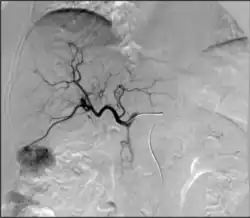

TACE

• Can be performed in different ways:

• Conventional transarterial chemoembolization (cTACE): Injection of lipiodol with high dose chemotherapy with or without microparticles directly into the tumor-feeding arteries.[66]

• Drug eluting bead transarterial chemoembolization (DEB-TACE): delivery of microparticles that are themselves loaded with the chemotherapy agent—typically doxorubicin or irinotecan.

• Chemoembolization: Combined injection of chemotherapy and embolic agents into the arterial blood supply of a tumor, with the goal of both local administration of chemotherapy, slowing "washout" of the chemotherapy drug, and also decreasing tumor arterial supply